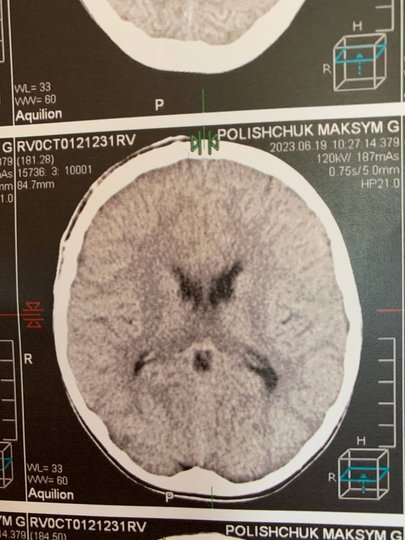

У Рівненській обласній дитячій лікарні прооперували 9-річного хлопчика, який отримав важку черепно-мозкову травму після ігор з однолітками. Хлопчик потрапив у лікарню після того, як його вдарили каменем по голові. Про успішно виконану операцію стало відомо у понеділок, 10 липня, після повідомлення прес-служби медзакладу.

У коментарі ZAXID.NET лікар-нейрохірург дитячий Сергій Романчук, який виконував операцію, розповів, що хлопчик потрапив у лікарню в важкому стані. Зокрема, він перебував без свідомості, але й були епізоди, коли пацієнт прокидався і перебував в стані психомоторного збудження: поводився неадекватно і не реагував на обстановку навколо.

За оцінками лікаря, операцію потрібно було проводити негайно, оскільки через гематому ділянка мозку, на яку тиснув кров'яний згусток, могла почати відмирати. Оперативне втручання розпочали близько 23:00, тривало воно впродовж 3,5 годин.

«Особливість цієї операції в тому, що це була велика гематома. Ми йому зняли невеликий фрагмент кістки, забрали гематому, і після цього кістку поставили назад і прифіксували спеціальними кістковими швами. Завдяки цьому в нього все швидко заросте і не буде косметичного дефекту», – зазначає Сергій Романчук.